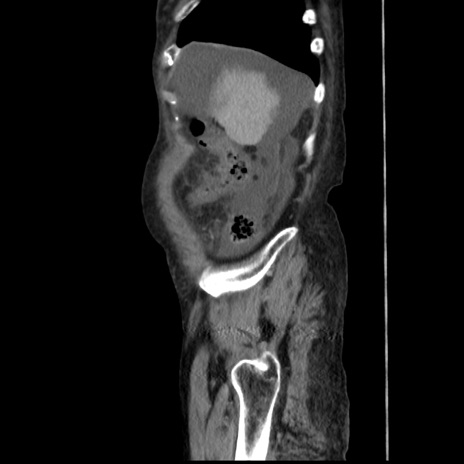

症例31(矢状断像)

【症例】80歳代 女性

【主訴】腹部膨満感

【現病歴】他院にて肝硬変にてフォロー中。1週間前から便秘、腹部膨満感、臍部腫瘤あり受診となる。

【既往歴】肝硬変

【身体所見】腹部膨隆あり、皮膚変化なし、疼痛なし。

【データ】WBC 4600、CRP 0.25